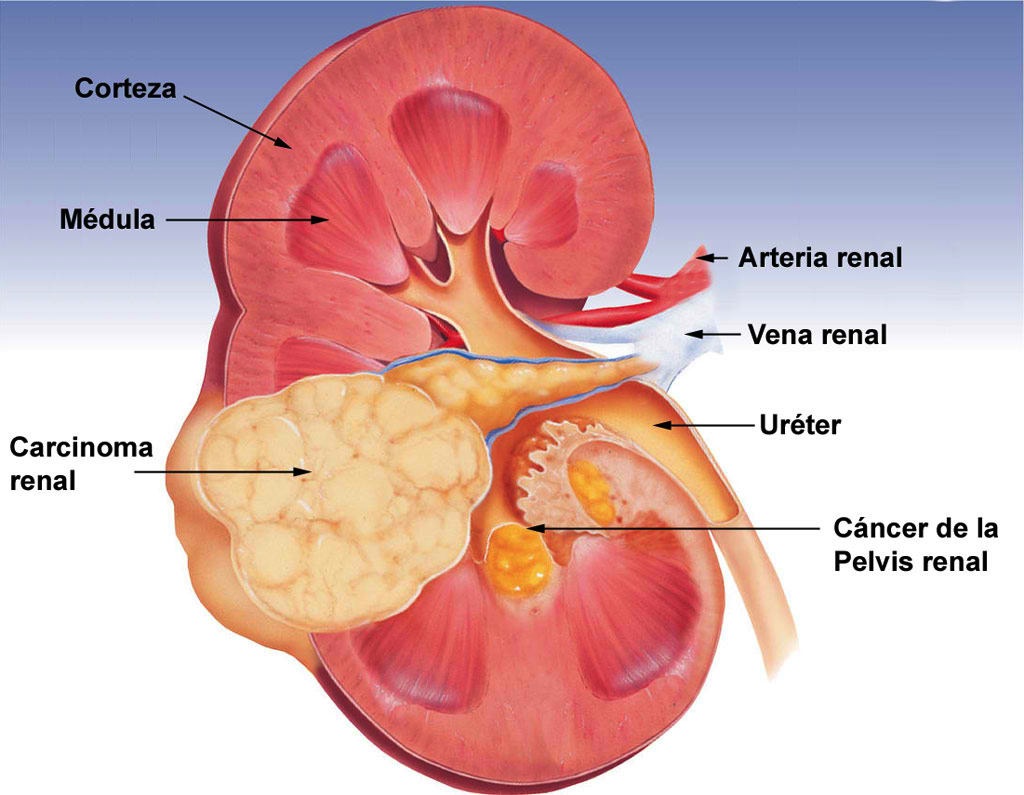

Puede curarse si se detecta pronto, pero a menudo da síntomas cuando tiene gran tamaño o se ha extendido a otros órganos.

Afecta el doble a los varones respecto a las mujeres. Es más frecuente en adultos a partir de los 50 años, aunque hay una variante, denominada tumor de Wilms, que afecta a los niños.

Los tumores renales de gran tamaño provocan sensación de tener un bulto y dolor en el abdomen, y aparición de sangre en la orina, pero los tumores pequeños son totalmente asintomáticos.

Se denomina Nefrectomía a la operación de extirpación del riñón.

Hablamos de Nefrectomía Parcial o Tumorectomía cuando se elimina la parte afectada pero se conserva el resto del riñón sano.

En caso de tumores grandes, se debe extraer la totalidad del riñón, con la grasa que lo rodea y los ganglios linfáticos regionales, en la denominada Nefrectomía Radical.

Si el tumor se origina en la vía urinaria, es preciso resecar además la totalidad del uréter y se efectúa la NefroUreterectomía.